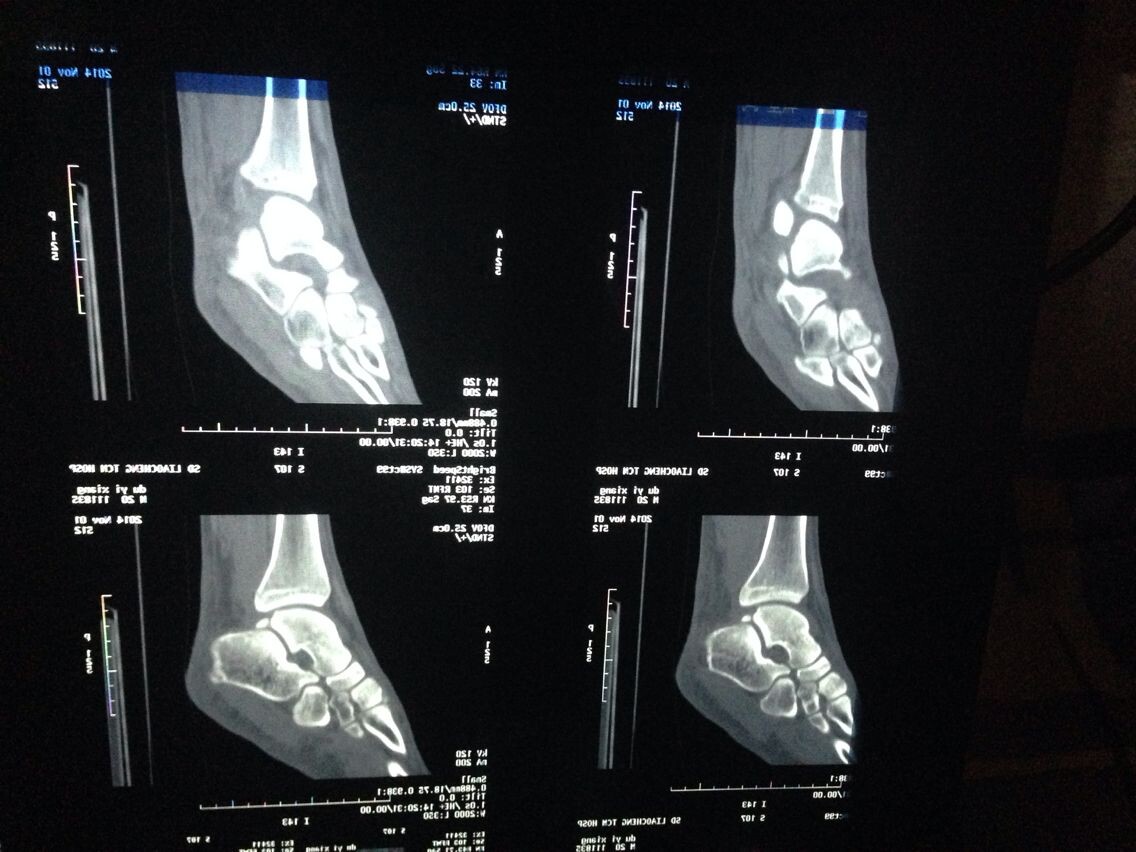

跪求看片啊。。。骨科。脚部

ct吧

谁能给我分析分析啊,,,,,医生也没说什么,有点敷衍

片子不全吧,顺序也很重要